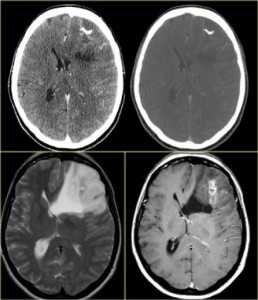

КТ и МРТ головного мозга. Аксиальные КТ, Т2-взвешенные МРТ и МРТ головного мозга с контрастировавшем. Вовлечение коры при олигодендроглиоме.

При МРТ головного мозга множественность очагов типична для метастазов (30-50%), глиобластом (5%), опухолей при факоматозах.

МРТ головного мозга. Аксиальные Т1-взвешенные МРТ с контрастировавшем. Множественные метастазы и двухстроронние шванномы при нейрофиброматозе тип 2.